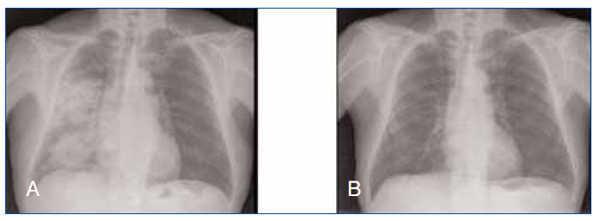

Dos años y 3 meses después de haberse positivizado los ANCA, y encontrándose con terapia inmunosupresora con ciclofosfamida a dosis de 50 mg/día por vía oral, se detectó la primera recaída de la enfermedad, con unos títulos de anti-MPO de 367 U/ml, manifestada por fracaso renal agudo no oligúrico (pico máximo de creatinina de 6 ,5 mg/dl), aparición de hematuria macroscópica y hemorragia pulmonar derecha (figura 1), que respondió al tratamiento con pulsos de 500 mg de 6-metilprednisolona i.v. (tres dosis), seguido de prednisona oral a dosis de 1 mg/kd/día y pulsos de 500 mg de ciclofosfamida. A los 2 meses de esta primera recaída, el paciente ingresó por otra infección respiratoria no condensativa con respuesta favorable con levofloxacino.

Figura 1. Hemorragia pulmonar en el hemitoráx derecho (A) antes de tratamiento y (B) tras recibir tratamiento inmunosupresor.